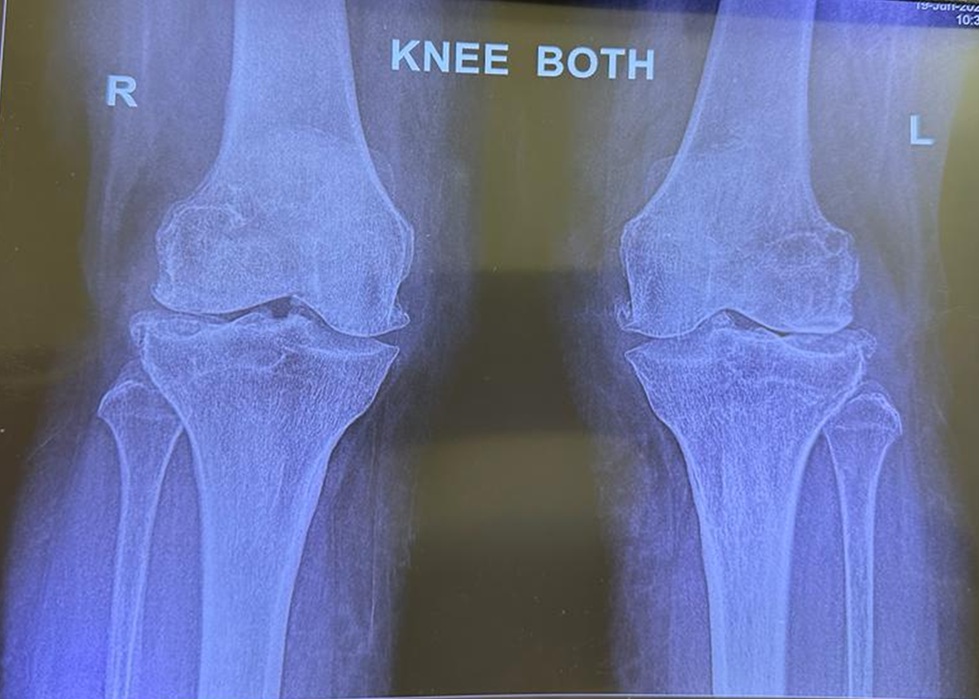

Real case example of arthritis and knee replacement

Before surgery. Both knees show severe joint space loss and bony changes, matching long standing pain and stiffness.

After surgery. Total knee replacement restores alignment and gives a smoother bearing surface for walking and daily activity.

Images are shared for education with identity protected. Every knee is different and final plans are always individual.

Diagnosis is clear. X rays confirm advanced arthritis that matches your pain and deformity.